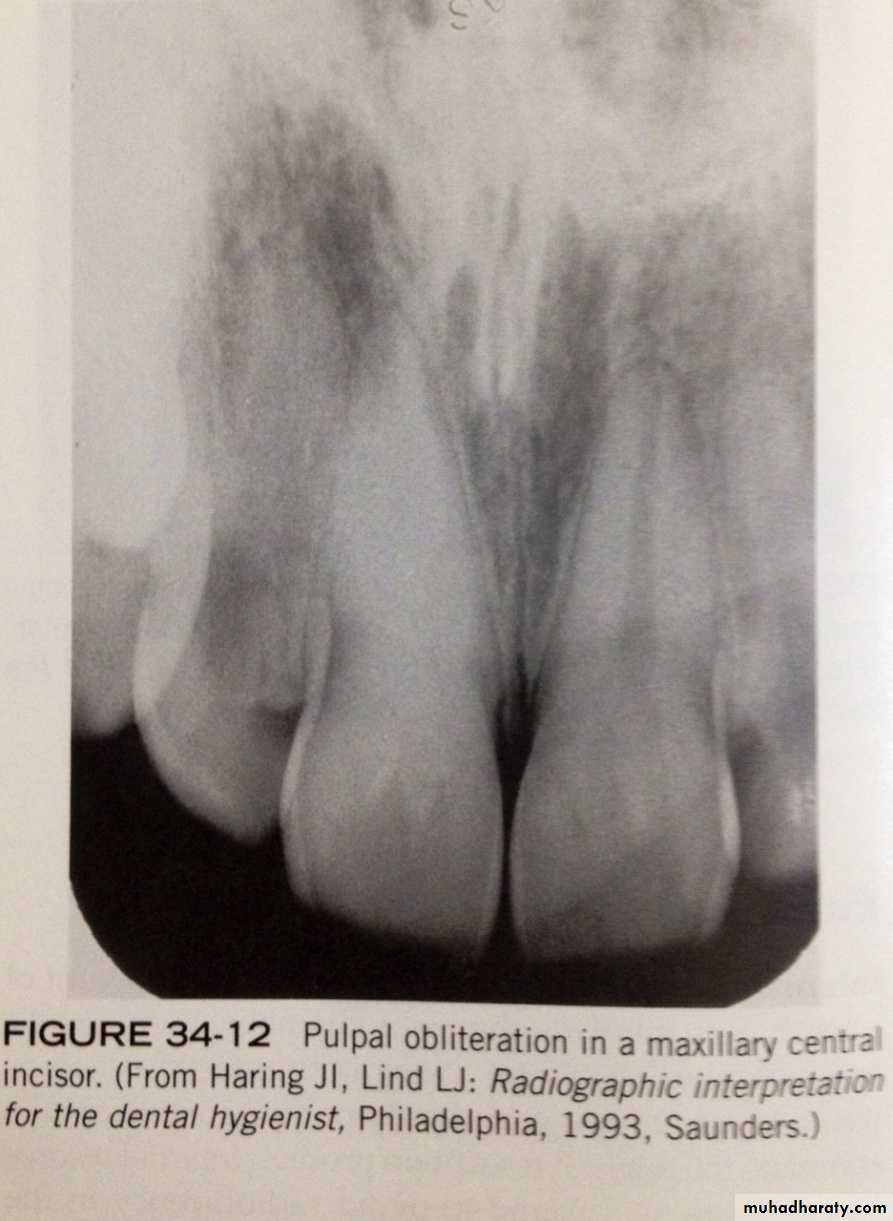

- is a diffuse calcification of pulp chamber and pupl canals of teeth that result decreased pulp cavity. its associated with aging. appear on radiograph incidentally and have little clinical significance.Pulpal obliteration:

some conditions( e.g: attrition, abrasion, caries, trauma) may act as irritant to the pulp and stimulate the production of secondary dentin, which results in obliteration of pulp. - radiographically: tooth with this condition does not appear to have pulp chamber or pulp canals and nonvital.Pulpal obliteration: